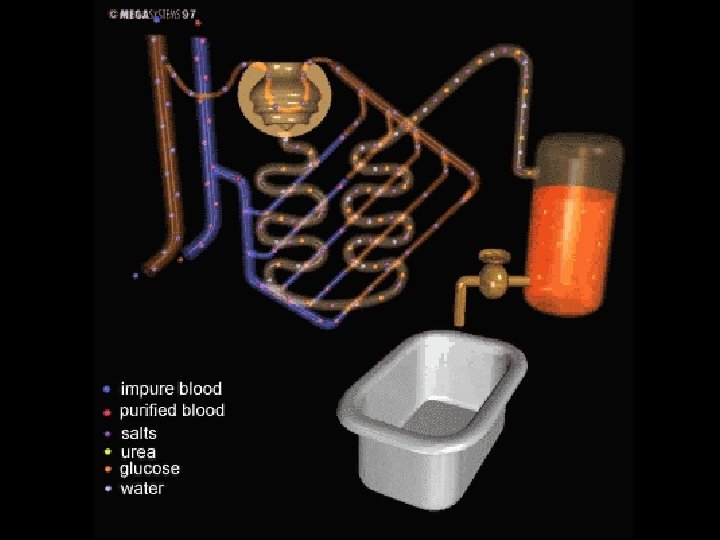

URINE FORMATION There are three steps during urine formation. 1. Filtration 2. Reabsorbtion 3. Secretion

FILTRATION • During filtration, substances pass from the blood into the Bowman’s capsule. • Under pressure, water and many small molecules such as salts, urea, glucose and aminoacids pass from glomerulus into Bowman’s capsule.

REABSORBTION • The absorbtion of needed materials such as glucose, amino acids and water from nephrons to blood capillaries is called reabsorbtion. • Water is reabsorbed passively by osmosis. But reabsorbtion of glucose, aminoacids and salt ions occurs by active transport.

• All glucose, aminoacids and many salt ions are reabsorb during reabsorption. • Most reabsorbtion takes places in loop of henle. • Antidiuretic hormone (ADH or Vasopressin) regulates concentration of water in blood. • It increases water permeablity of the cells of the distal tubules.

SECRETION • The cells of distal tubule excrete molecules such as penicilin, ammonia, potassium and excess acids. This process is called secretion. • After secretion, the fluid remaining in the nephrons is called urine. • Urine contains urea, uric acid, sodium, potassium, calcium, chlorine, phosphorus, water and small amount of cells.